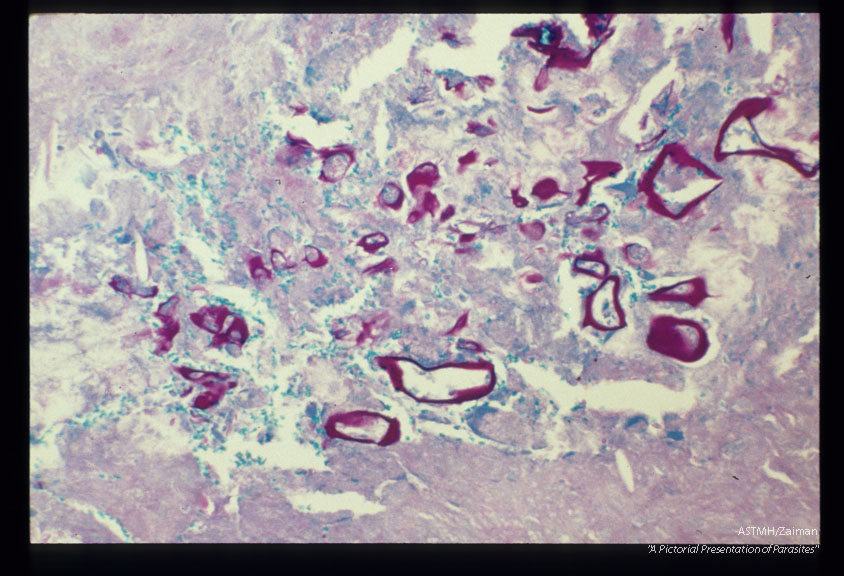

PAS stain of infected human liver.

Echinococcus multilocularis

Description: PAS stain of infected human liver.